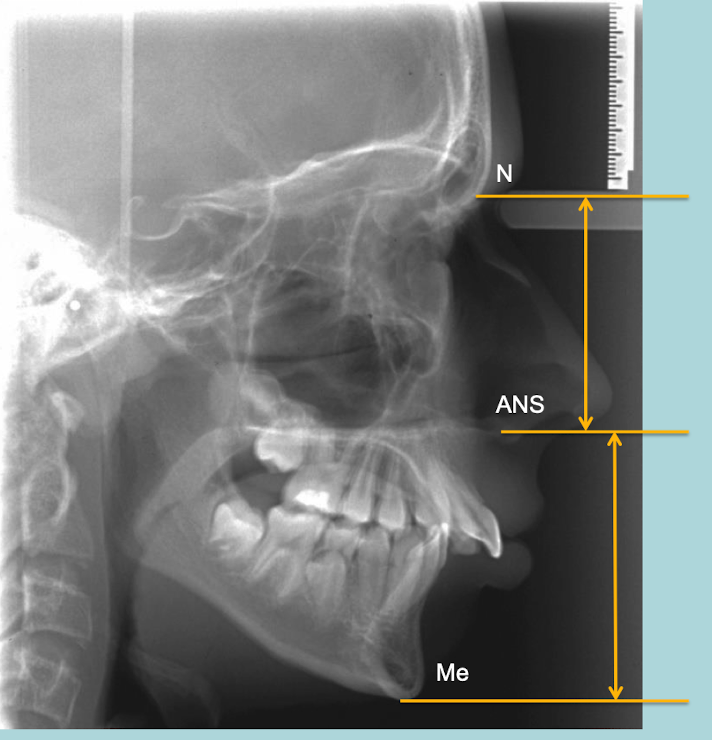

ceph landmarks for upper/ lower anterior face height

• nasion

• anterior nasal spine

• menton